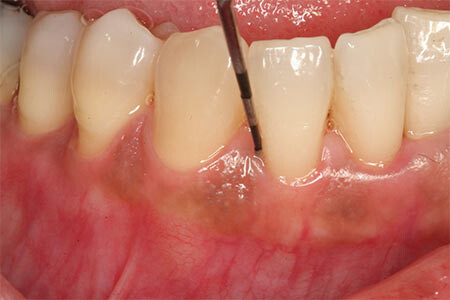

Suppose you're experiencing any warning signs of gum disease, such as bad breath, bleeding, red and swollen gums, or receding gum tissue. In that case, it's imperative to have your dental professional examine your mouth. Beyond a visual assessment of your gum tissue, your dental professional will measure the pocket depth around each of your teeth with a periodontal probe. This allows them to determine the presence of periodontal disease and how far it has progressed.

Did you know that a dental professional can probe six different sites around your tooth during a periodontal examination? The National Institutes of Dental and Cranial Research (NIDCR) defines periodontal disease parameters as a tooth with at least one periodontal site with a pocket that's 4 millimeters or more in depth and 3 millimeters or more in attachment loss. When the tissue that attaches the gum to the tooth breaks down, the gum will recede, and bone support of the tooth is lost, causing teeth to become loose.